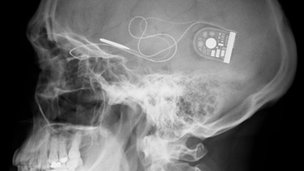

X-ray of skull showing position of chip with cable running to control unit

The surgery involves placing it behind the retina from where a fine cable runs to a control unit under the skin behind the ear.